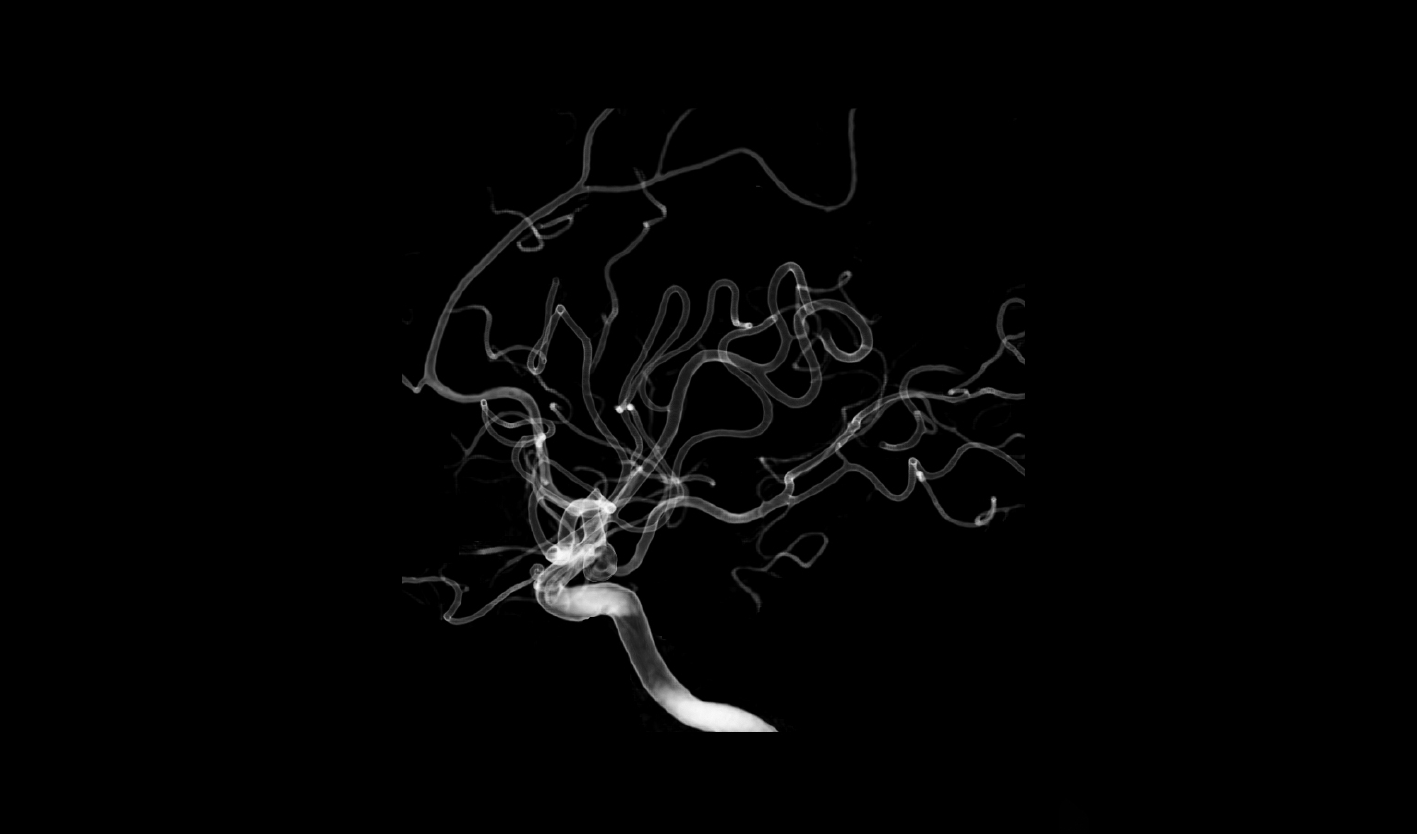

精微小血管可視

2K超清影像鏈,精至微小血管一覽無余

分辨率高